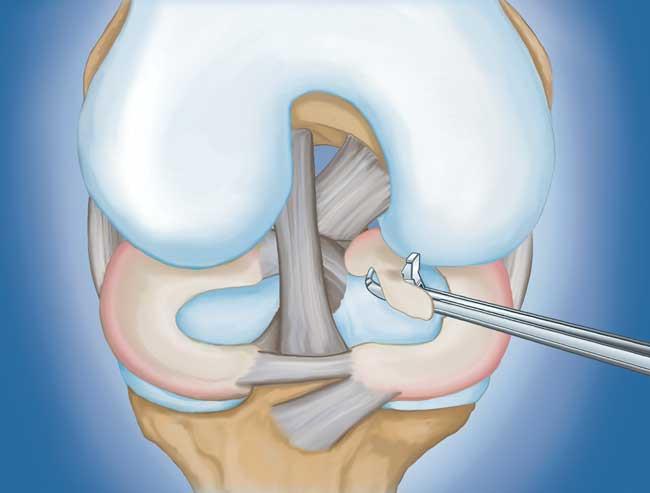

Διαδικασία. Η αρθροσκόπηση γόνατος είναι μια από τις πιο συχνά πραγματοποιούμενες χειρουργικές επεμβάσεις. Σε αυτήν τη διαδικασία, ο χειρουργός εισάγει μια μικροσκοπική κάμερα μέσω μιας μικρής τομής (πύλης) στο γόνατο. Αυτό παρέχει μια καθαρή εικόνα του εσωτερικού του γόνατος. Στη συνέχεια, ο χειρουργός εισάγει χειρουργικά εργαλεία μέσω δύο ή τριών άλλων μικρών πυλών για να κόψει ή να επιδιορθώσει τη ρήξη.

- Επισκευή μηνίσκου. Ορισμένες ρήξεις μηνίσκου μπορούν να επισκευαστούν με συρραφή (ράψιμο) των σχισμένων τμημάτων μεταξύ τους. Το αν μια ρήξη μπορεί να επισκευαστεί με επιτυχία εξαρτάται από τον τύπο της ρήξης, καθώς και από τη συνολική κατάσταση του τραυματισμένου μηνίσκου. Επειδή ο μηνίσκος πρέπει να επουλωθεί ξανά, ο χρόνος αποκατάστασης για μια επισκευή είναι μεγαλύτερος από ό,τι για μια μηνισκεκτομή.